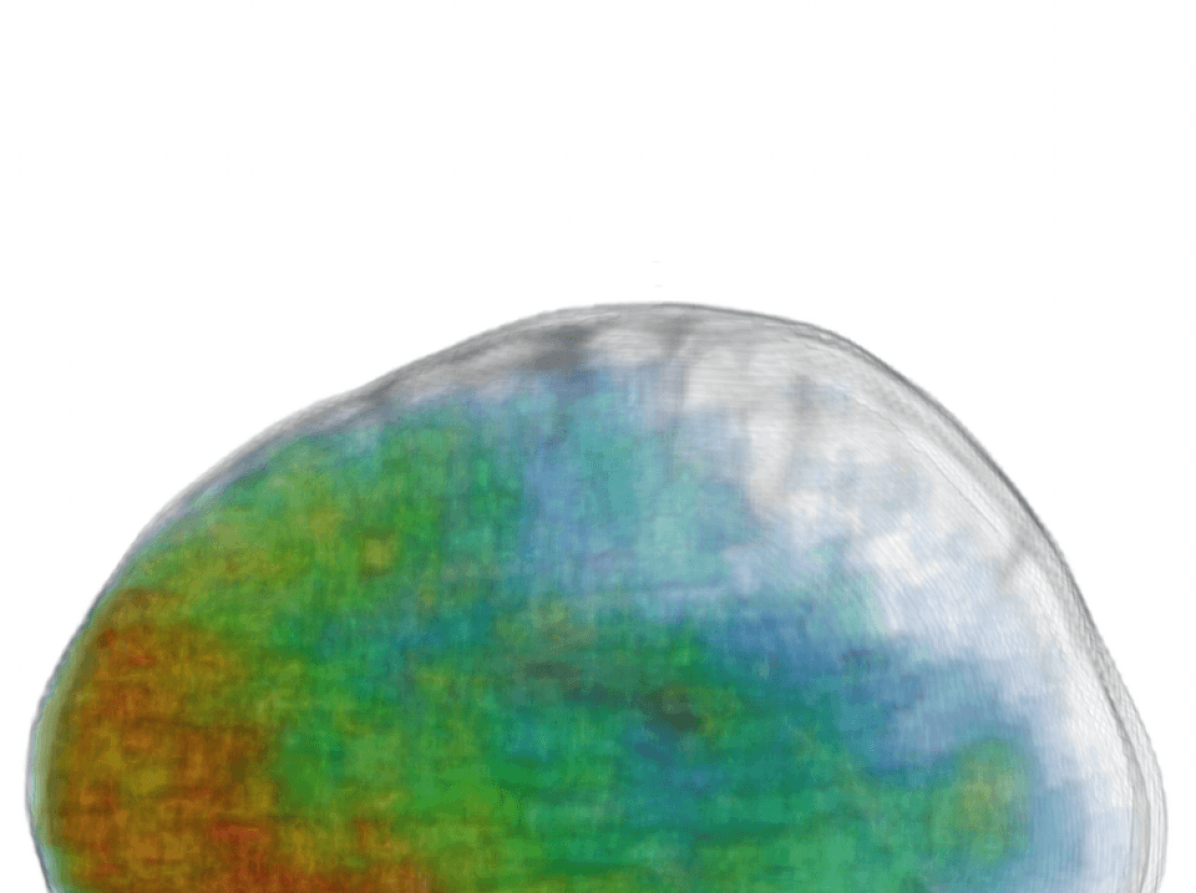

Similarly intriguing is the information extracted in the low-resolution pathway. As they process greater context, these neurons gain additional localization capabilities. The activations of certain FMs form fields in the surrounding areas of the brain. These patterns are preserved in the deepest hidden layers, which indicates they are beneficial for the final segmentation (see two last rows of Fig. 14). We believe these cues provide a spatial bias to the system, for instance that large TBI contusions tend to occur towards the front and sides of the brain (see Fig. 1(c)). Furthermore, the interaction of the multi-resolution features can be observed in FMs of the hidden layer that follows the concatenation of the pathways. The network learns to weight the output of the two pathways, preserving low resolution in certain parts and show fine details in others (bottom row of Fig. 14, first three FMs). Our assumption is that the low-resolution pathway provides a rough localization of large pathologies and brain areas that are challenging to segment, which reserves the rest of the network’s capacity for learning detailed patterns associated with the detection of smaller lesions, fine structures and ambiguous areas.